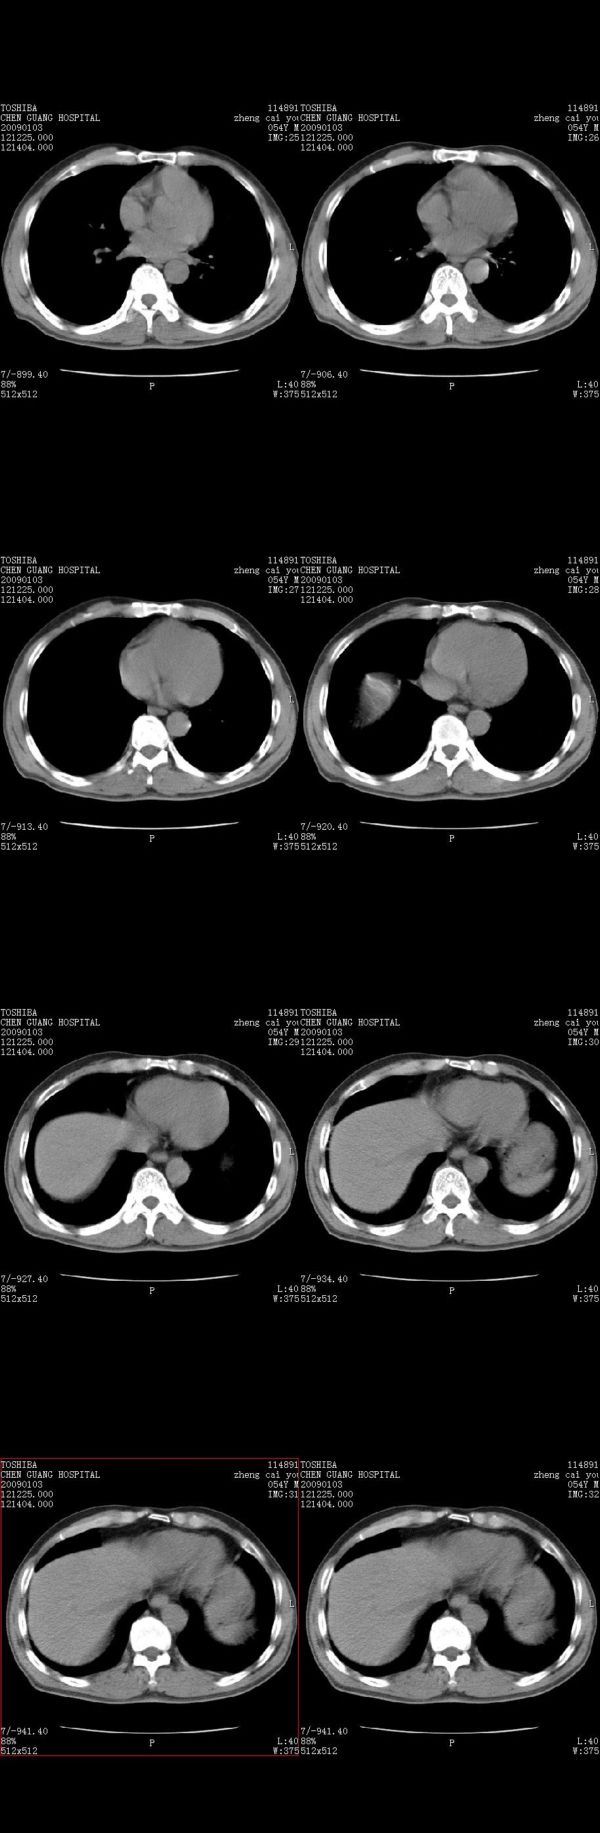

男,54岁,右侧胸部疼痛,平时吸烟,有抽烟后咳嗽咯痰史。昨天没把xiphoid软件吃懂,所以没把纵隔窗图像处理出来!请各位老师帮忙看一下右肺门有没有问题?谢谢!!!!!!!!!!

右肺上叶后段近气管旁仍可见一结节灶,不除外为肿大的淋巴结影。

气管前腔静脉后似见增大淋巴结影,肺门区未见明显肿块影。肺窗示右肺中叶外侧段透亮度增高,可过一段时间再查一下对比一下,毕竟是自己的至亲,又有条件,辐射就顾不得了。

也觉得还好吧,只是右下肺动脉显粗了点,纵膈有钙化淋巴结,再有肺窗就更好了

右侧肺门影增大,不除外增大淋巴结可能